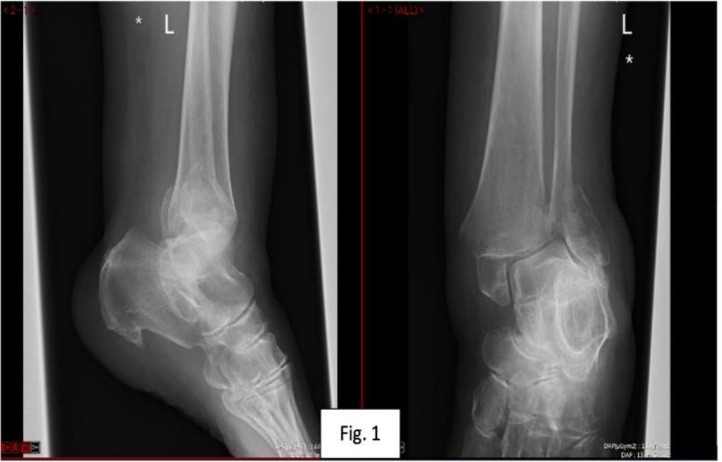

Here we present a novel adaptation of the previously described fibula pro-tibial fixation in a case requiring salvage fixation of a bimalleolar ankle fracture in an osteoporotic patient. Unstable osteoporotic ankle fractures are a challenging injury to manage and typically occur in a frail and comorbid subgroup of patients. Various techniques have been described in the evolution of managing these injuries, e.g. hindfoot nailing and anatomical locking plates, however in this uniquely challenging case a novel strategy was required to mitigate bone loss in the distal fibular fracture fragment. There is some evidence to suggest fibular protibial fixation offers a lower complication profile to its alternatives. The novel use of distal fibula pro-tibial screws offers a new alternative to hindfoot nailing of bimalleolar ankle fracture in osteoporotic bone with compromised distal fibular fragment bone purchase. Further research is required to investigate the compatibility of this technique with early weightbearing.

Abstract Image